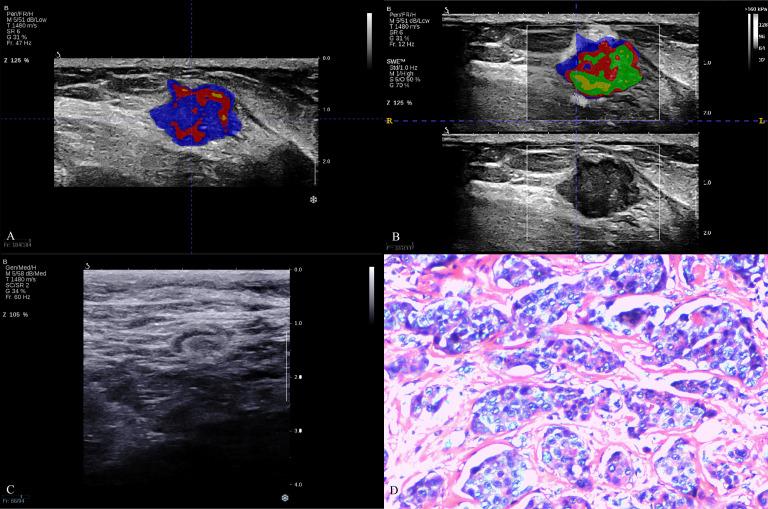

A total of 206 patients with 206 breast lesions were enrolled in this study from July 2019 to December 2023. All patients were randomly divided into training cohort (165 patients) and test cohort (41 patients). The feature extraction was manually delineated with ITK-SNAP software, while a K-means clustering algorithm was employed for the segmentation of sub-regions, with the number of clusters ranging from 2 to 10. Radiomic features were extracted separately from the subregions of B-mode ultrasound (BMUS) and shear wave elastography (SWE) images after habitat generation. These modality-specific features were then combined. Eleven machine learning models were used to build models, including support vector machines (SVM), k-nearest neighbor (KNN), RandomForest (RF), ExtraTrees, XGBoost, light gradient boosting machine (LGB), NaiveBayes, AdaBoost, GradientBoosting, LR and MLP. Prediction performance was compared among clinicopathological model, omics models and habitat models.

According to the habitat analysis results of K clustering for BMUS and SWE, the omics features of 4 subregions for BMUS images and the 5 subregions for SWE images were extracted respectively. Compared the prediction performance of the clinicopathologic (C) risk factors model, habitat and omics models in the test cohort, NaiveBayes model based on SWE habitat achieved the highest prediction performance with AUC of 0.953 (95% CI: 0.893, 1.000).

Habitat analysis based on ultrasound might be a potential method to visualize the intratumoral heterogeneity of breast lesions. The machine learning models based on SWE radiomics with habitat analysis could enhance the ability of prediction lymph node burden in patients with early-stage breast cancer, which could be a promising approach to make clinical decisions.